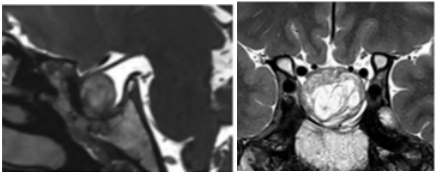

能否完全切除肿瘤取决于多种因素,包括肿瘤的一致性和侵袭性。许多放射影像学特征是手术结果不佳的标志,如多叶的巨大腺瘤、骨质侵袭和海绵窦受累。对功能性和无功能性腺瘤(图1)两者,改良Knosp分级是一个用来预测肿瘤切除率的有用的工具,它描述了腺瘤与颈动脉的关系。

图1.垂体腺瘤改良Knosp分级